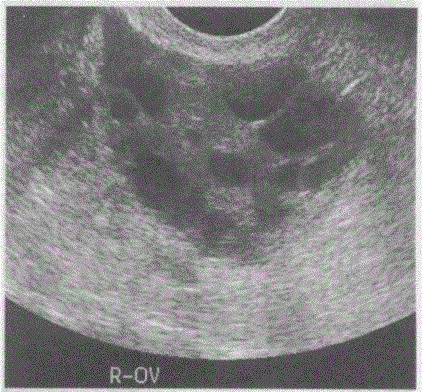

问题 临床资料:女,29岁,自述自幼肥胖,多毛,月经稀少,结婚5年不孕。 化验检查:雄激素与睾酮升高。 超声综合描述:经阴道扫查,子宫小,内膜显示不清;双侧卵巢均匀性增大。包膜光滑增厚回声增强,每个超声切面可见>10个大小不等无.回声区,最大直径0.9cm,透声清亮。 超声提示:

选项 A.多囊卵巢综合征 B.葡萄胎 C.卵巢过度刺激综合征 D.正常卵巢声像图

答案 A